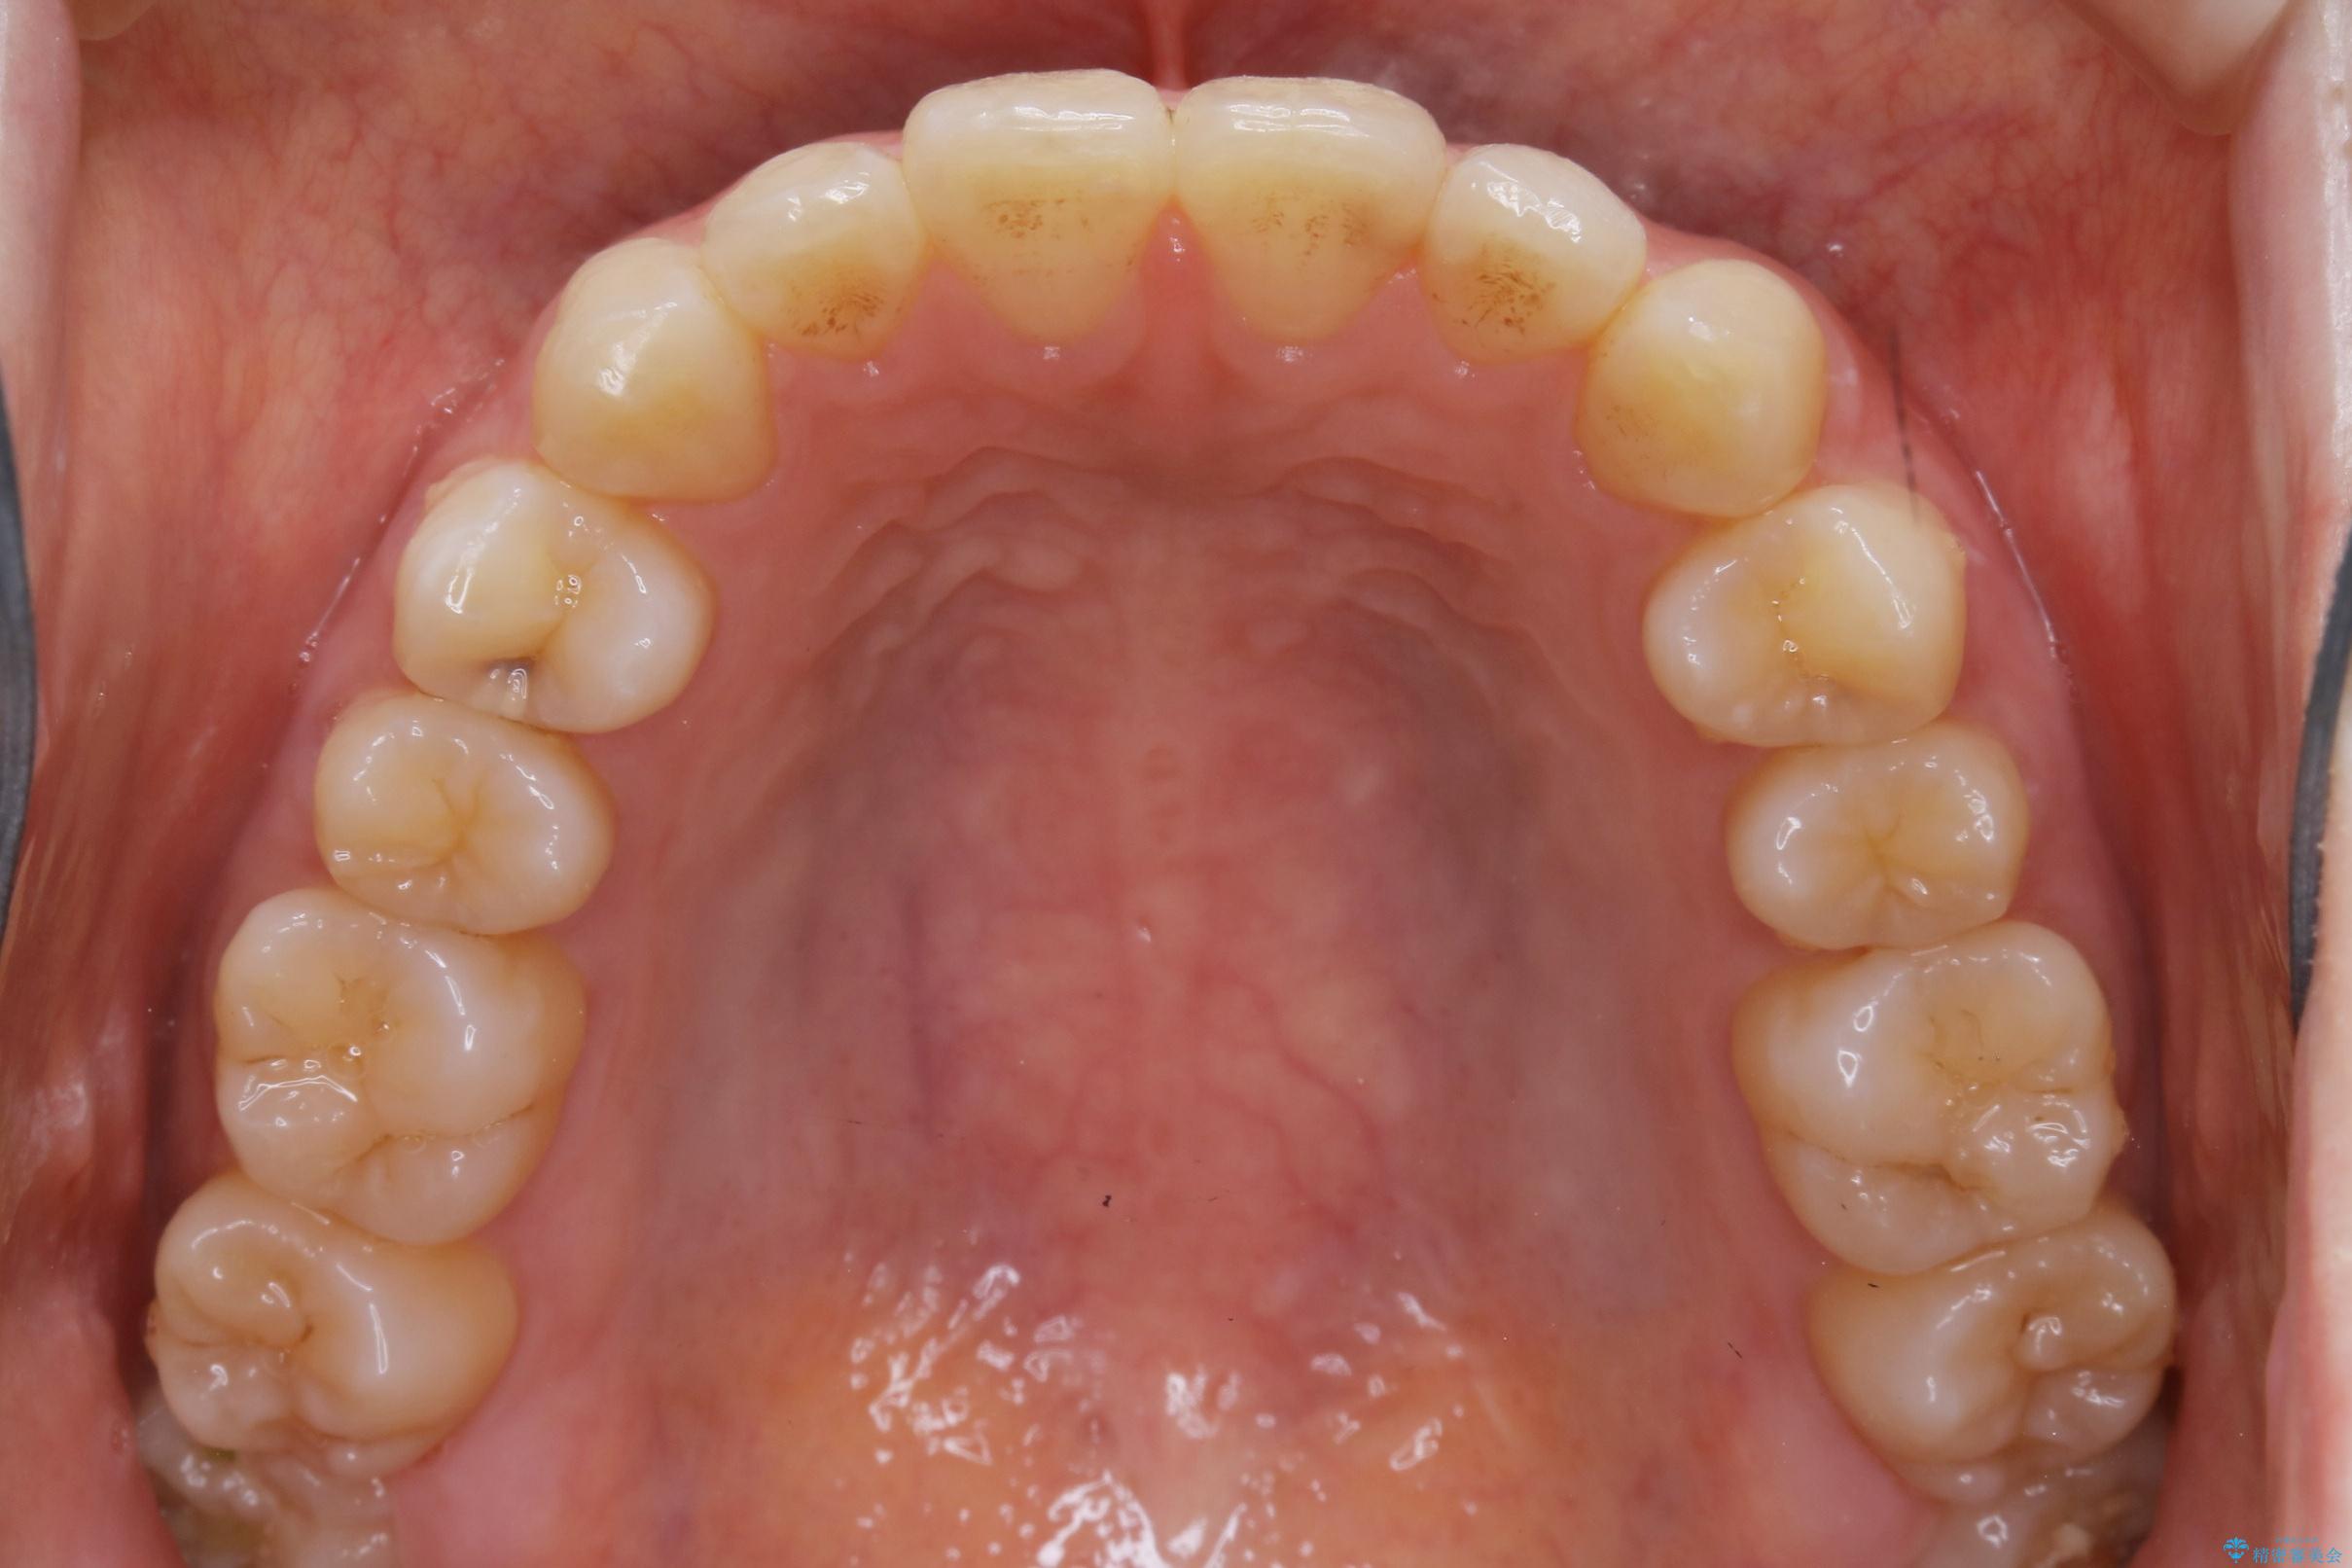

20代 女性 インビザラインで短期間矯正

- 20代女性

- 1年

- 49.5万円(インビザライン ライトパッケージ)

下の前歯のガタつきが気になるとご来院された患者様です。

インビザラインのライトパッケージにて、歯列拡大とディスキング(IPR)をを行いスペースをつくり非抜歯で治療を行いました。